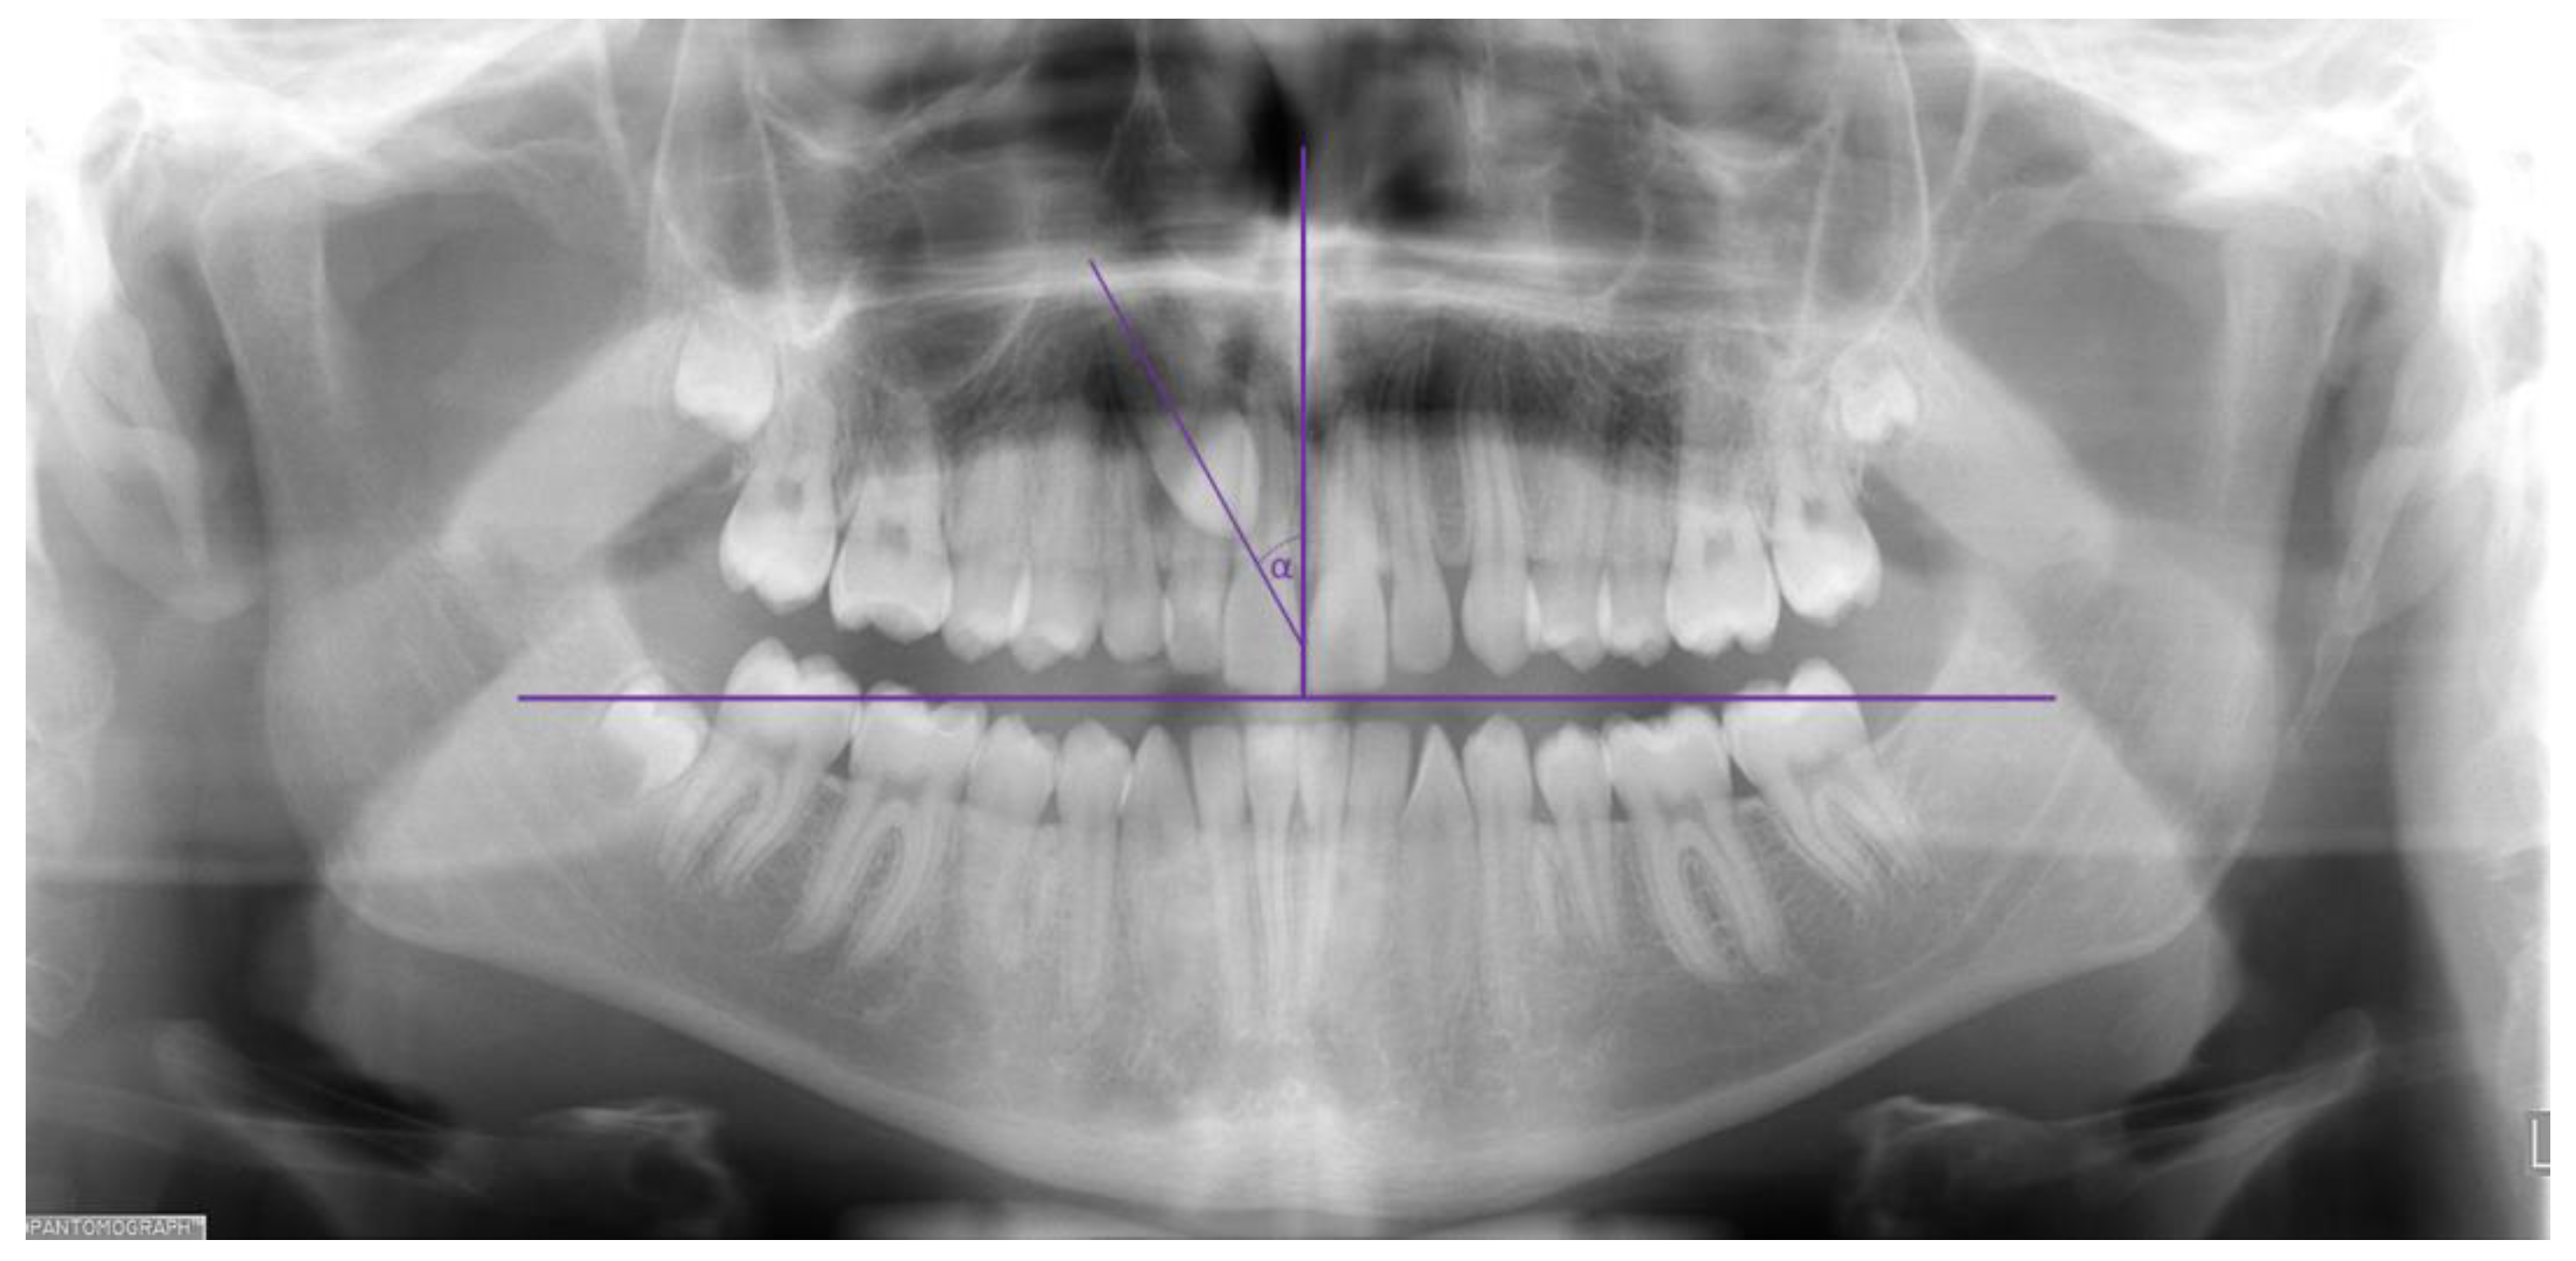

| Canine axis angle | Median | 40° | 0° | * p < 0.001 (Mann-Whitney test)  |

| Interquartile range (25–75%) | 32.5–49° | 0–5° |

| Canine axis angle | Median | 39° | 5° | * p < 0.001 (Mann-Whitney test)  |

| Interquartile range (25–75%) | 30.5–49° | 0–31° |